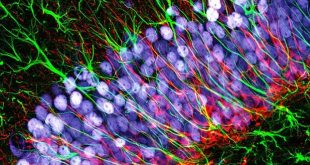

نوروسافاری | پژوهشگران موفق شدند سلول جدیدی که در درمان بیماریهایی از جمله ام.اس موثر است، کشف کنند. التهاب مغز، یکی از نشانههای ام.اس، آلزایمر و برخی اختلالات روانی است. پژوهش جدیدی نشان میدهد که شاید بررسی نوعی سلول مغزی بتواند به کشف درمانهای جدیدی برای بیماریهای مربوط به …